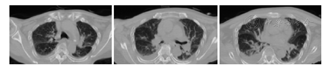

辅助检查结果:5月2日行血、尿、便常规,生化,肿瘤标志物检查,结果均正常。5月3日行心脏和腹部超声未见明显异常。头颅MRI(5月11日)示:双侧侧脑室周围及额顶叶皮质下腔隙性梗死、缺血灶;脑萎缩(图1)。24 h脑电图(5月10日):清醒期两侧大脑半球轻度慢波活动,睡眠期见少量散发及短阵尖波、尖慢波,颞顶区偏胜,5月10日晨视频见肢体抽搐发作,同时见右侧颞区短暂可疑尖波发放,痫样放电可能(图2)。胸部CT(5月1日):慢性支气管炎样改变伴两肺感染,两下肺间质略增生;主动脉硬化,左心室增大;两侧胸腔少量积液;两肺尖胸膜增厚、钙化(图3)。

The chest CT findings of the patient on May 1,2018 suggested two pulmonary infections